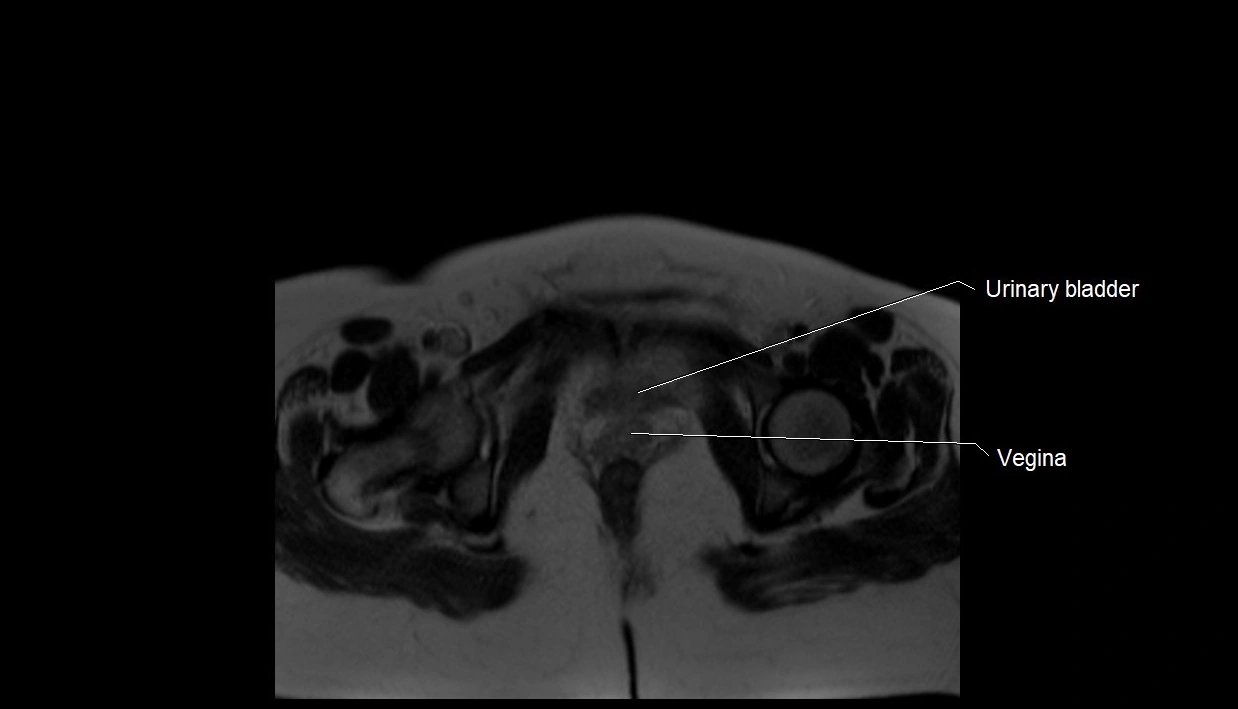

MRI Appearance

T2 HASTE (T2 GRE):

• Amniotic fluid shows very bright hyperintense signal

• Provides natural contrast against fetus and placenta

• Small particles (vernix) may appear as scattered hypointense foci within bright fluid